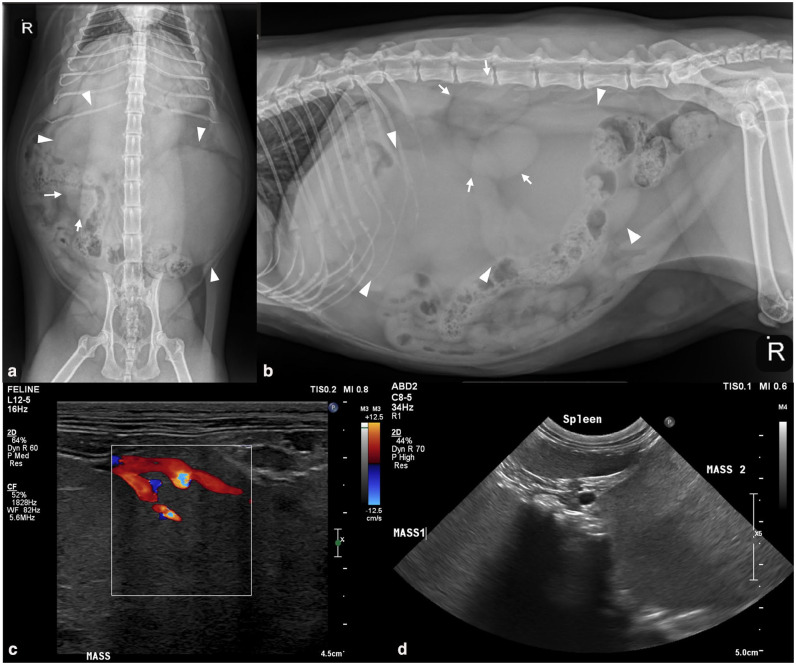

病例总结:一只6岁雌性家养短毛猫因腹胀和体重减轻而出现。腹部x光片和超声显示两个颅腹部肿块和另一个靠近空肠的肿块。颅腹部肿块的细胞学特征与外分泌胰腺组织一致。4个月后,复查腹部超声显示腹部肿块进行性增大和内侧髂淋巴结病。在剖腹探查时,两个腹部肿块与胰腺有关,并合并了供应肝脏、胰腺和脾脏的大血管。肿块不能切除,行切口活检。组织学特征可诊断为外分泌胰腺腺癌的透明化亚型。没有进行化疗。在最初发现腹部肿块后的28个多月里,这只猫还活着,据报道状况良好。相关性和新信息:据作者所知,这是猫胰腺腺癌透明化亚型的首次报道。这种亚型被认为在狗身上表现得不那么咄咄逼人,这个案例可能支持类似的,更懒惰的行为可能在猫身上看到。

Case summary: A 6-year-old female spayed domestic shorthair cat was presented for abdominal distension and weight loss. Abdominal radiographs and ultrasound revealed two cranial abdominal masses and another mass adjacent to the jejunum. Cytologic features of the cranial abdominal masses were consistent with exocrine pancreatic tissue. Four months later, a repeat abdominal ultrasound revealed progressive enlargement of the abdominal masses and medial iliac lymphadenopathy. On exploratory laparotomy, two abdominal masses were associated with the pancreas and incorporated large blood vessels supplying the liver, pancreas and spleen. The masses were non-resectable and incisional biopsies were obtained. The histologic features were diagnostic for a hyalinizing subtype of exocrine pancreatic adenocarcinoma. Chemotherapy was not pursued. Over 28 months after the initial detection of abdominal masses, the cat was still alive and reportedly doing well.